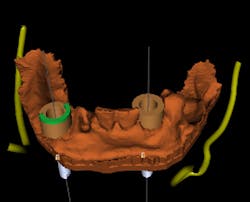

A polyvinyl siloxane (PVS) impression is taken of the remaining mandibular teeth. A CBCT scan is taken of the patient without a scan guide, and a CBCT scan is taken of the PVS impression in the mouth. The impression scan can be inverted and aligned with the patient’s CBCT scan in the implant planning software. This gives an accurate digital representation of the bone as well as the dentition (figure 2).

A stable guide can rest on just two teeth, and also can take some tissue support if necessary. The implants can be placed as immediate implants, provided enough teeth remain to support the guide. In this case, the right lateral (No. 26) is virtually extracted and implants are planned for sites Nos. 23 and 26. A tooth-supported guide is designed and 3-D printed (figure 3).